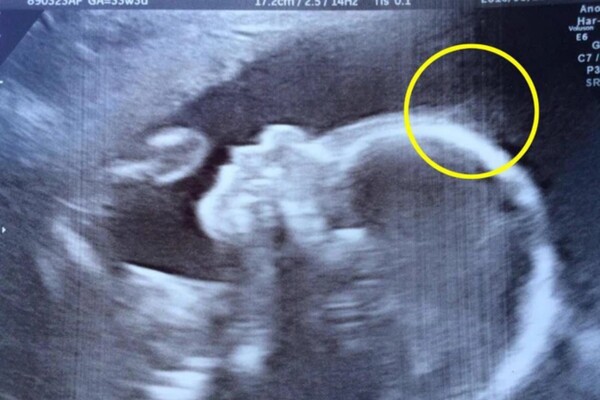

Cũng giống như rất nhiều bà bầu khác, chị Natasha Gent, 28 tuổi, đến từ thành phố Medway, hạt Kent, phía Đông Nam nước Anh, cũng đi khám định kỳ. Tuy nhiên, khi đến viện để siêu âm ở tuần thứ 20, chị Natasha đã được bác sĩ thông báo về một điều đặc biệt, điểm lạ trên cơ thể con gái khiến chị không khỏi hoang mang, lo lắng.

Hình ảnh siêu âm cho thấy ở trán của em bé có rất nhiều sợi như tóc lởm chởm ở trên, điều này rất ít khi thấy ở những đứa trẻ khác. Nghe bác sĩ kết luận, ban đầu, chị Natasha và gia đình không khỏi hoảng sợ vì nghĩ có thể con đang mắc bệnh gì đó.

Nhưng bác sĩ đã giải thích và khẳng định rõ rằng, điểm đặc biệt này trên đầu em bé hoàn toàn không gây ra nguy hiểm và không ảnh hưởng gì đến sức khoẻ của đứa trẻ. Thậm chí, vợ chồng Natasha còn không thể ngờ rằng, chính nó lại trở thành dấu hiệu để con gái trở thành một "ngôi sao" ngay từ khi chào đời.